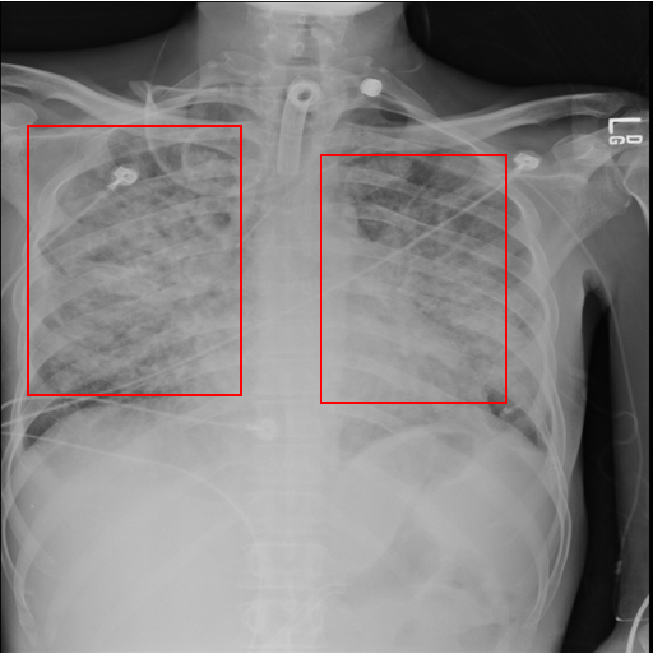

Pediatric Pneumonia Chest Xray Kaggle Pneumonia Detection On Chest X Ray Using Radiomic Features And Contrastive Learning In this study, we proposed a novel framework that leverages radiomics features and contrastive learning to detect pneumonia in. In this study, we proposed a novel framework that leverages radiomics features and contrastive learning to detect pneumonia in. This study proposed a novel framework that leverages radiomics features and contrastive learning to detect pneumonia in. In this study, we proposed. Pneumonia Detection On Chest X Ray Using Radiomic Features And Contrastive Learning.